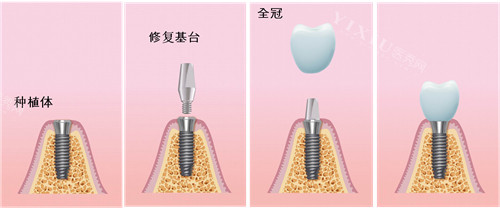

天悦口腔采用的智能化种植技术,通过CBCT比较准扫描、3D模拟种植方案设计,实现小创口不痛种植体验。国产创英种植体作为主打产品,其四级纯钛材质与骨结合性能优异,5年临床使用成功概率高达98.2%,与韩国登腾种植体97.6%的成功概率相当,但价格更为亲民。

针对骨量不足患者,天悦口腔提供多种骨增量解决方案,包括引导骨再生术(价格3000元起)、上颌窦提升术(价格4500元起)等辅助项目,确保种植体长期稳定性。术后提供长期免费复查服务,这在东莞地区属于较为完善的服务支持体系。